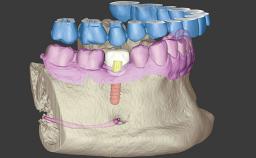

Replacing a Mandibular Denture with a Full-Arch Implant-Supported Mandibular Fixed Dental Prosthesis

This case describes an all-digital approach to a common patient complaint: dissatisfaction with denture stability while chewing. A 68-year-old male patient with a mandibular complete denture opposing a full-arch maxillary provisional fixed dental prosthesis (FDP) presented for an implant consultation. His medical history was non-contributory, and there was no contraindication to dental implant treatment.